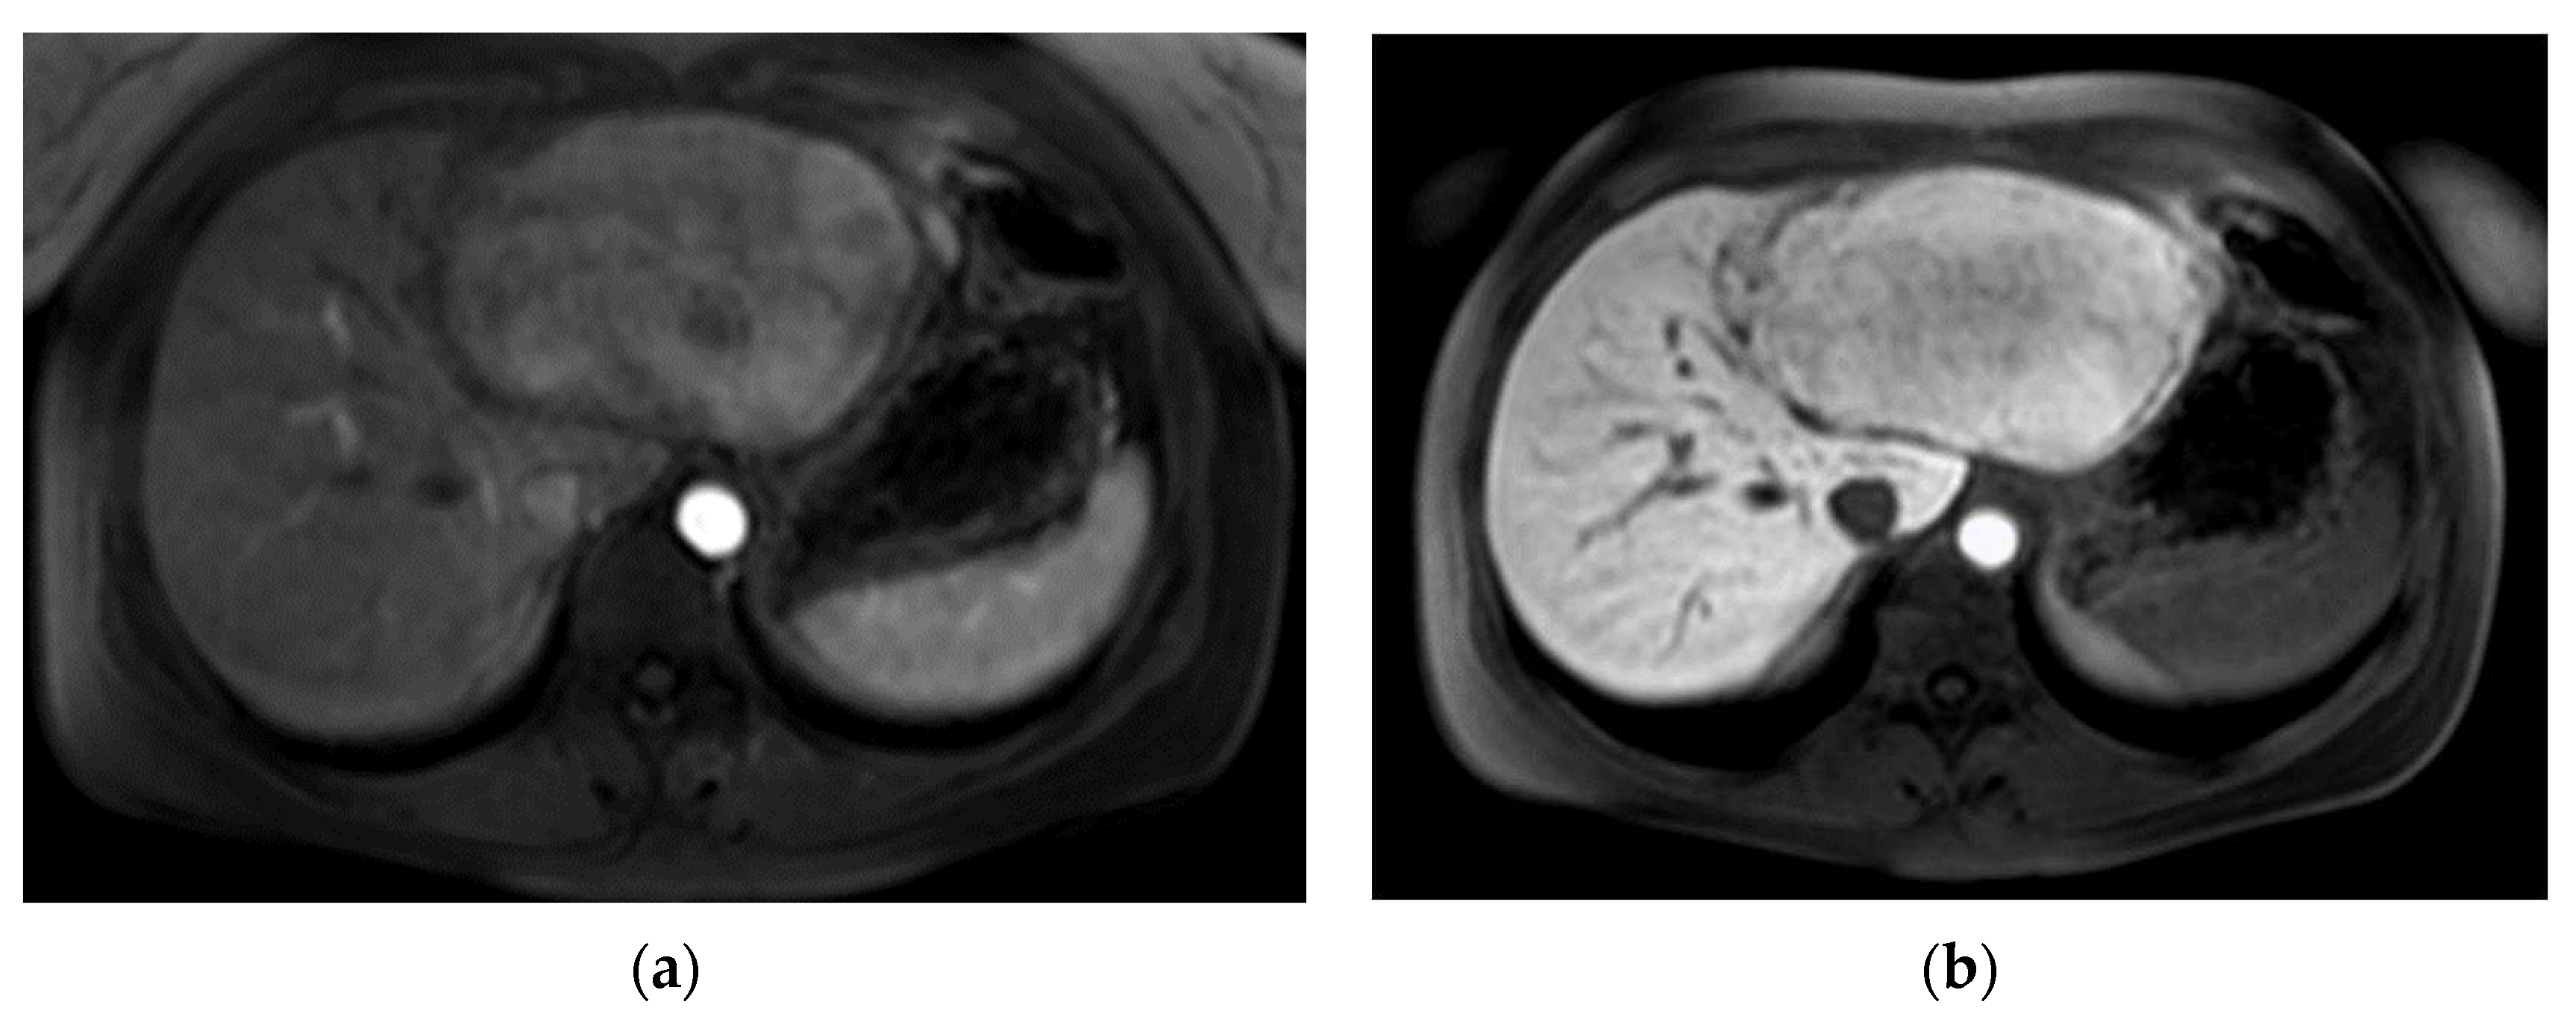

The second patient was referred to our out-patient clinic with a liver lesion of the left lobe, which had been growing constantly over 7 years. A FNH had been diagnosed at the age of 23, which met the typical MRI-criteria including contrast retention in hepatobiliary imaging and the patient was in regular follow-ups (Figure 2). Because of the tumor growth and inhomogeneity along the tumor capsule we performed a left hepatectomy (H234′) (Figure 2d). The final histological findings revealed a HCC and the patient is in regular follow-ups since without evidence of recurrence for over 44 months until today.

Figure 2. Pre-operative MR imaging Patient 2: (a) Arterial phase imaging depicting hyperenhancement of liver lesion; (b) T1 sequence with fat saturation in hepatobiliary phase depicting isointensity to liver; (c,d) T1 sequence with fat saturation post contrast showing size progression from (c,d) in 3 years.